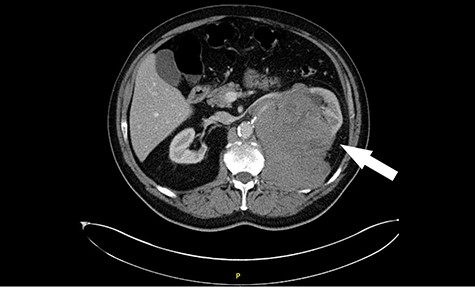

His CT scan identified large left renal tumour invading psoas muscle. Left mid ureteric tumour as well. Multiple regional nodes. No hepatic, pulmonary or osseous metastasis. The scan was highly suggestive of metastatic transitional cell carcinoma (Figs. 1 and 2).

Computed tomography (CT) sagittal section showing predominant bulk of the mass is extrarenal that posteriorly breaches the fascia to involve the diaphragm and psoas muscle. Medially it reaches the intervertebral foramen.